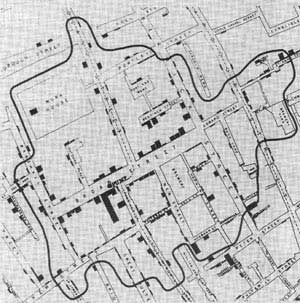

特别值得注意的应用出现在约翰·斯诺(John Snow)对1854年伦敦霍乱疫情的分析中。以下地图包括在斯诺(Snow)关于威斯敏斯特大教堂圣詹姆斯教区霍乱疫情的报告中(1854年秋天),显示了死亡人数的分布由于霍乱。每个小条表示该地址处的死亡人数。

|

| 点击放大 |

然后,斯诺考虑了饮用水的来源,遍布整个城市的水泵,并划出了一条标有“宽街泵与其他水泵之间的距离相等的边界”的线,从本质上说明了宽街泵的Voronoi单元。

该地图支持斯诺的假说,即霍乱死亡与受污染的水有关(在本例中为宽街泵)。斯诺建议当局移开泵的把手,此后霍乱爆发迅速结束。由于斯诺的工作帮助发展了现代流行病学领域,因此该地图被称为“最著名的19世纪疾病地图”。